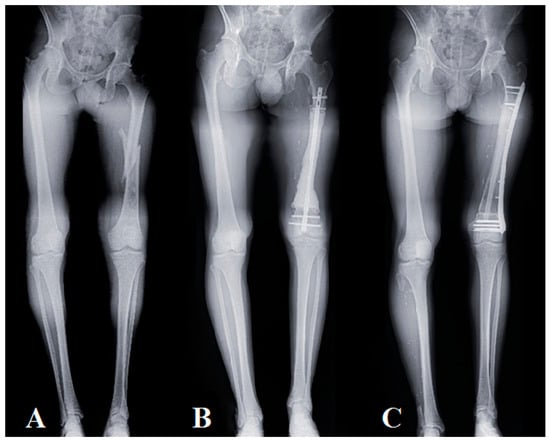

Stabilization was achieved with a large LCP plate; the graft was held in place by at least two single cortical screws. Finally, compression was applied at both interfaces after the autologous graft bone from the reaming was added (Figure 3).

Figure 3.

Progression of a Capasquelet technique reconstruction, using a pangonogram X-ray view, in a 28 year old patient with high-grade osteosarcoma (patient No. 2): (A) preoperative X-ray, fractured high-grade osteosarcoma with a length inequality of 80 mm; (B) postoperative X-ray of the 1st surgical stage after carcinologic resection and placement of the spacer on an intramedullary nail with a length inequality of 60 mm (post-T1 delay: 1 month); (C) postoperative X-ray at 1 year, residual lower limb inequality of 40 mm.